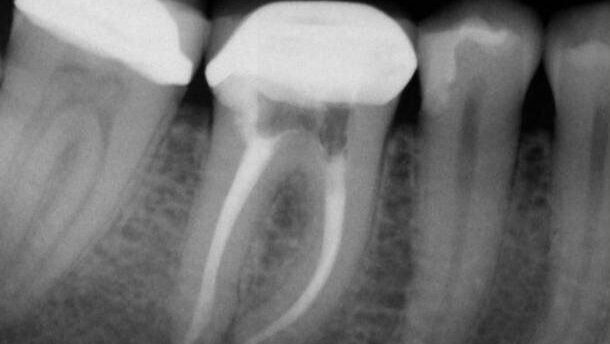

Wobec wyzwania, jakie dla lekarzy praktyków stanowią bakterie, techniki rewizji leczenia endodontycznego muszą umożliwiać eliminację bakterii i ich substratów. Wykorzystanie mikroskopu zabiegowego i narzędzi ultradźwiękowych pozwala lekarzom odnaleźć wszystkie szczegóły budowy anatomicznej kanałów i całkowicie oczyścić system kanałów korzeniowych. Przedstawiony przypadek (Ryc. 4a, b) ilustruje zakres przestrzeni wewnątrzkorzeniowej, która pozostała nienaruszona po pierwotnym leczeniu endodontycznym ze względu na brak dostatecznego otwarcia kanału policzkowego mezjalnego oraz niezlokalizowany i nieoczyszczony, ukryty dodatkowy kanał policzkowy mezjalny.

Endodontyczne końcówki ultradźwiękowe bardzo skutecznie usuwają materiał odbudowujący zrąb zęba, materiały wypełniające w postaci pasty, wkłady korzeniowe oraz wypełnienia ze srebrnym ćwiekiem, jak przedstawiono na rycinie 5. Narzędzia te pozwalają lekarzowi na oszczędną preparację zębiny korzeniowej, ponieważ zapewniają doskonałą widoczność w mikroskopie zabiegowym, w ten sposób znacznie poprawiając możliwość skutecznej rewizji leczenia kanałowego (Ryc. 6a-c). Urządzenia emitujące ciepło, np. końcówka Systemu B (Axis, SybronEndo), umożliwiają wydajne usuwanie gutaperki i materiałów na bazie żywic z 1/3 dokoronowej kanału. Za pomocą pilników ręcznych i maszynowych można usunąć z kanału materiał wypełniający i nadać kanałom prawidłowy kształt na całej długości roboczej. Współczesne maszynowe pilniki ze stopu NiTi są bardzo elastyczne i odporne na złamanie. Pozwalają na mechaniczne poszerzenie wierzchołkowej 1/3 kanałów korzeniowych w sposób bezpieczny i wydajny, nie powodując zmiany naturalnej morfologii kanału. Dzięki temu możliwe jest skuteczne płukanie kanałów i dotarcie płynu do złożonych struktur anatomicznych w okolicy wierzchołków, gdzie bakterie mogą ukrywać się i przetrwać pomimo oczyszczania kanałów.